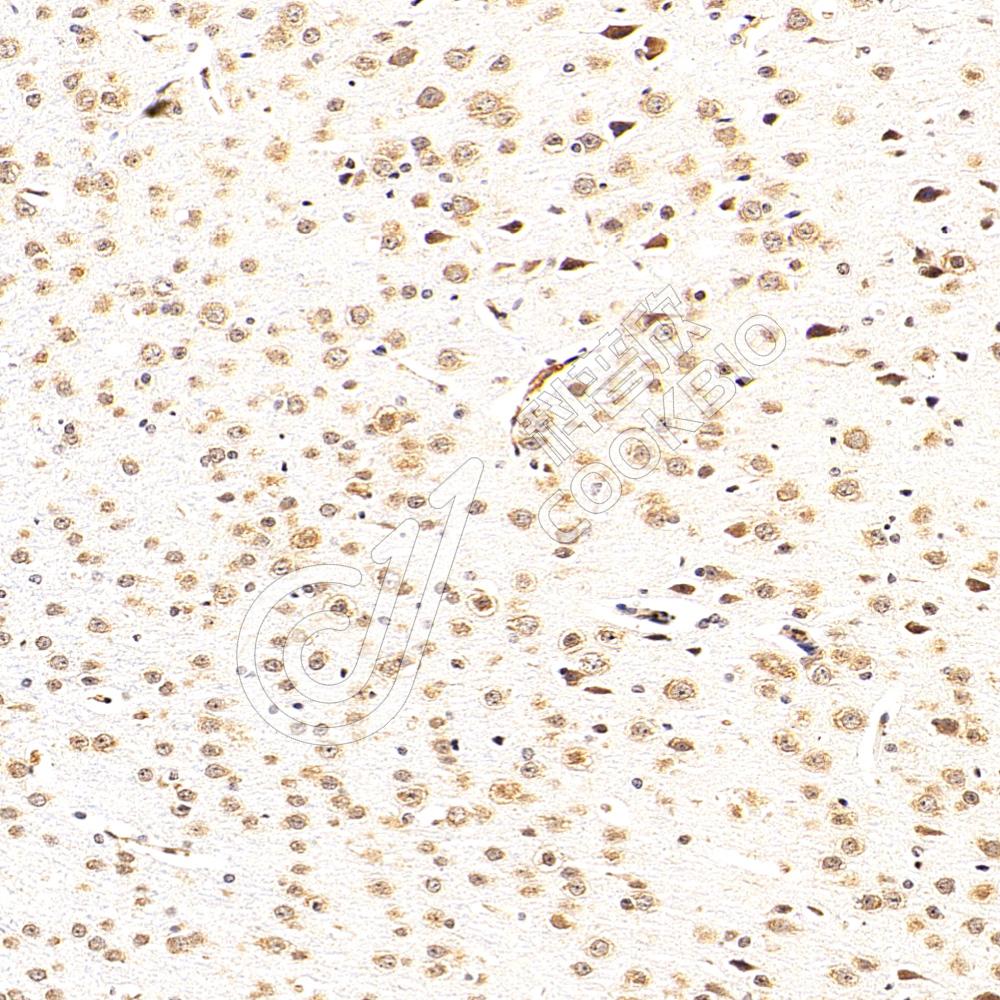

IHC检测ZIP Kinase蛋白(货号 K1335721).

样品: 小鼠脑, 4%多聚甲醛 (货号KSG1101) 固定12-24小时.

抗原修复: 柠檬酸抗原修复液(干粉, pH 6.0) (KSG1201), 98℃, 20分钟.

—抗: 1: 1300稀释, 4℃ 孵育过夜.

二抗: S-vision免疫组化多聚二抗(山羊抗兔),即用型 (货号KB3906), 室温孵育20分钟.